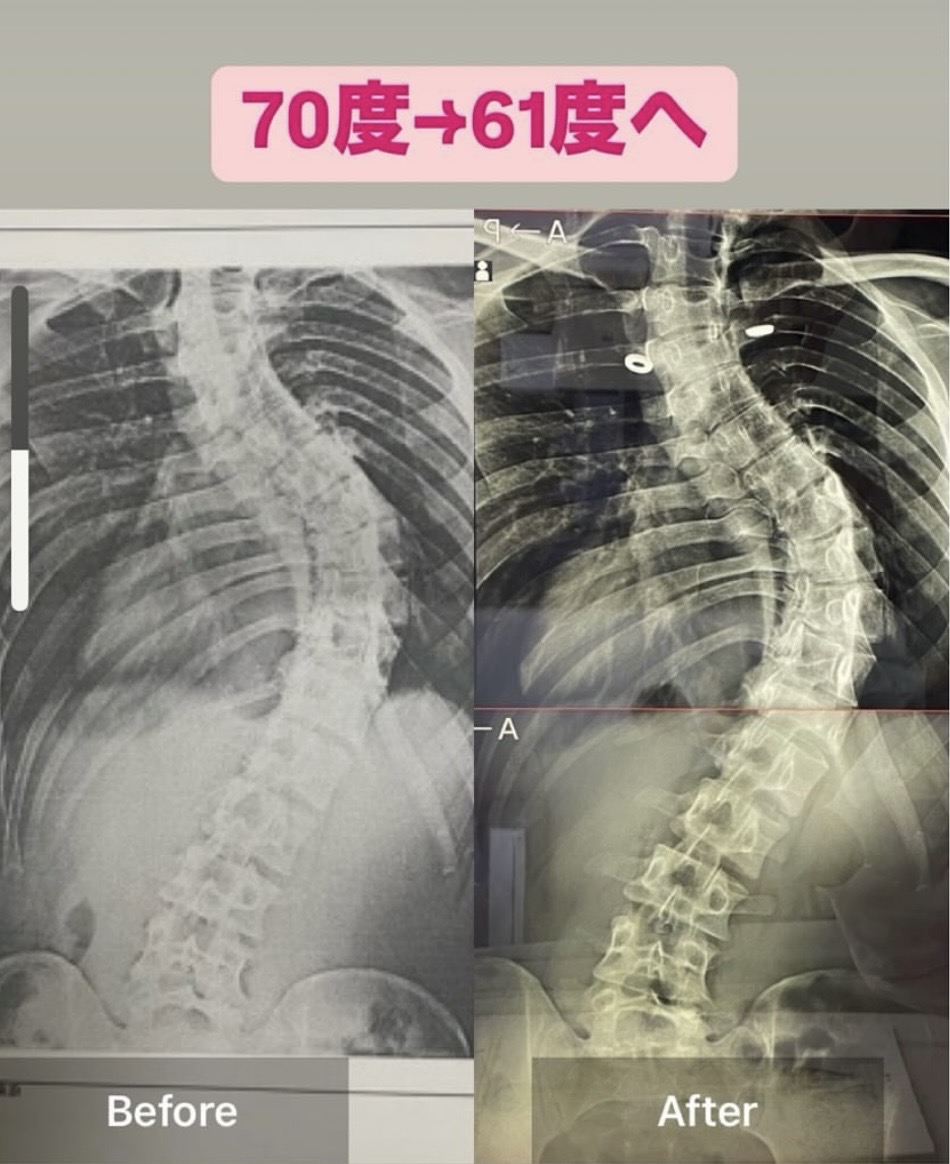

特発性側弯症のお客様によるレントゲンでのビフォーアフター3

(レントゲン上に角度の表記が無いため画像の比較で掲載しており

先生の所に通ってから5ヶ月経って先日改めてレントゲンをとりに

61度まで戻ってました。

驚きです!

施術を受ける前は70度です。

約10度良くなってました!